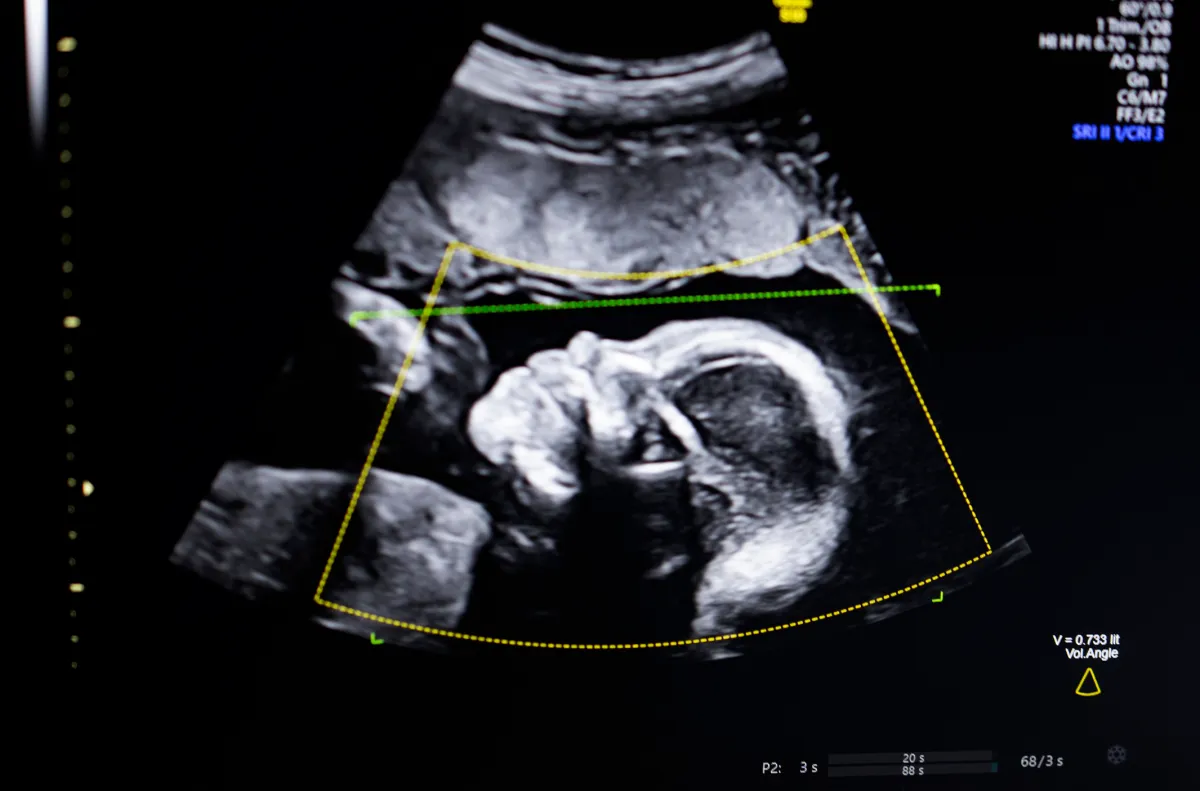

تستخدم التكنولوجيا رؤية الكمبيوتر الذكية “لدعم تقييم جودة الموجات فوق الصوتية الجنينية، والكمال التشريحي، والتقارير الآلية، والتكامل السلس في سير العمل السريري”، وفقًا لما قاله بستاني لصحيفة TechCrunch.

قال بستاني إن الموجات فوق الصوتية قبل الولادة أصبحت “الركيزة الأساسية” لمتابعة الحمل، ولكن صورها ذات الجودة المنخفضة يمكن أن تؤدي إلى تشخيص خاطئ.